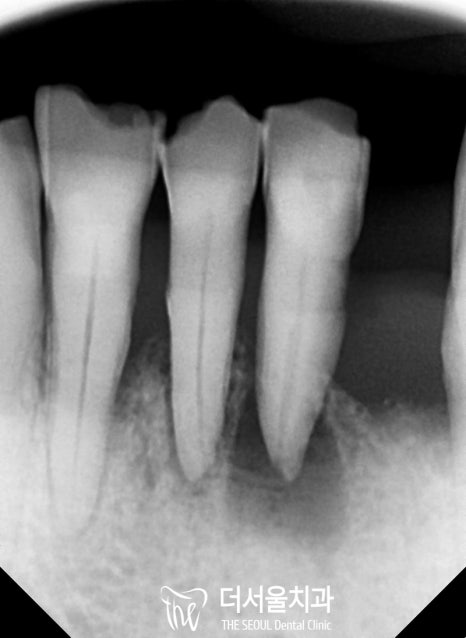

구강 내 사진을 보여드리면, 맨 뒤편에 있는

치조골, 그리고 앞쪽의 폭경이 심하진 않지만

좁아져 있는 것을 볼 수 있죠?

이 부위에 소량의 뼈 이식재를 이식하는,

골유도 재생술(GBR)을 진행해야 되는 상황입니다.